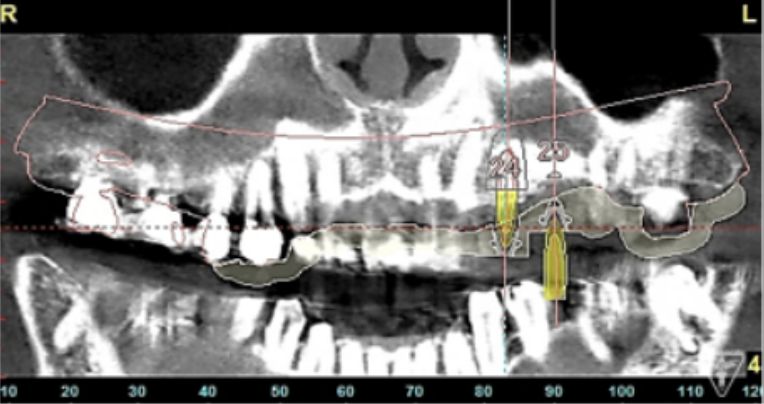

インプラント埋入前のCTによる確認